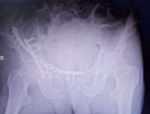

髖臼雙柱骨折行髂腹股溝入路聯(lián)合后側(cè)KL入路及術(shù)后并發(fā)癥分析探討 關(guān)鍵疾?。?a href="http://m.akellydesign.com/tags/so/右側(cè)髖臼雙柱骨折-4-1.html" target="_blank">右側(cè)髖臼雙柱骨折 現(xiàn)病史【一般資料】 男性,70歲,農(nóng)民 【主訴】 外傷致頭暈、右側(cè)髖部疼痛、活動(dòng)受限三小時(shí) 【現(xiàn)病史】患者三小時(shí)前干農(nóng)活時(shí)被其他車輛碰倒自兩米高處摔下,右下肢及臀部先著地,右側(cè)髖部不敢活動(dòng),傷后無(wú)意識(shí)消失,頭暈不適,有惡心,無(wú)嘔吐,急送至我院,門診攝片示“右側(cè)髖臼雙柱骨折,骨折累及臼頂,移位明顯”,門診予收住入院。病程中患者體溫正常,有頭暈、惡心,無(wú)嘔吐,傷后未進(jìn)食,大小便未解。 【既往史】十年前右眼因青光眼行手術(shù)治療。否認(rèn)“高血壓”“糖尿病”“冠心病”病史,否認(rèn)“肝炎”,“結(jié)核”等傳染病史,否認(rèn)...